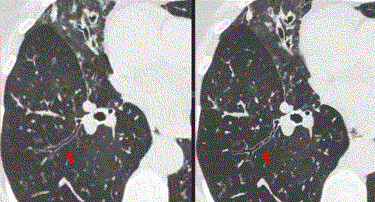

In clinical studies reported in the journal Radiology, up to 47% noise reduction was achieved with the new PCD-CT systems. ‘Noise’ refers to the random nature of X-ray signals, which makes the images more difficult to interpret because of the associated speckle pattern that overlies the true structures in the image.

The PCD-CT systems also have better spatial resolution when compared to the conventional systems. In studies, the system achieved the best reported resolution for a clinical CT system. McCollough compared it to a digital camera — the higher the number of megapixels, the finer details one can see.